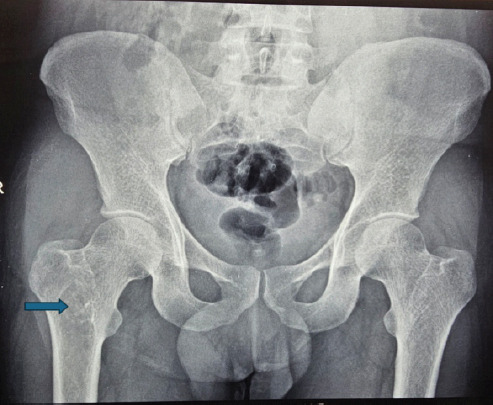

Case report: A 31-year-old apparently normal Indian male presented with pain and swelling of his right proximal femur for 8 months without any history of trauma. He also reported a similar swelling in his chest wall with allergic respiratory symptoms for 8 years. Laboratory analysis revealed mild elevation in inflammatory markers. Magnetic resonance imaging of the pelvis revealed osteolytic lesions in the right proximal femur and pubic bone with soft tissue collections, and computed tomography scan of the chest showed an osteolytic lesion in the right 9th rib with an overlying soft tissue collection and a subpleural cavitary nodule in the left lower lobe posterior basal segment. Although initially treated as a case of clinically diagnosed tuberculosis, the patient did not get any relief with antitubercular therapy. Fine needle aspiration cytology and fungal culture identified Cryptococcus neoformans from both lesions and from the blood culture. The patient responded well to antifungal treatment and is currently symptom free.